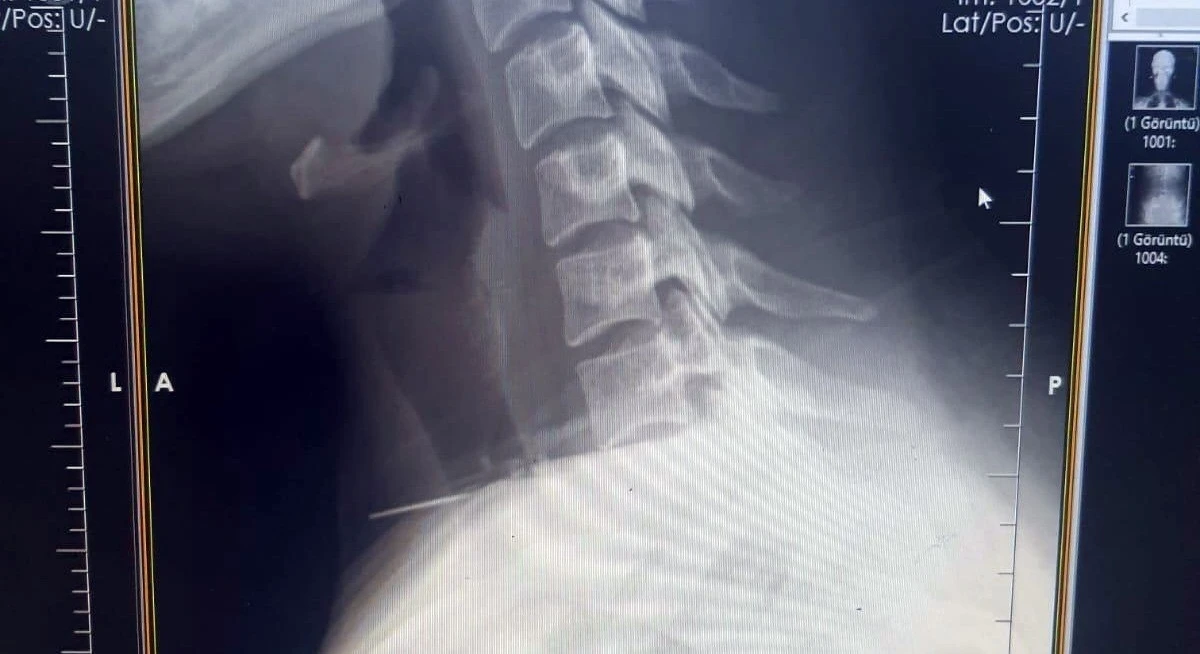

Kadının Boğazına Saplanan İğne Başarılı Bir Ameliyatla Çıkarıldı

Boğaza saplanan bir iğne nasıl bu kadar derine ilerledi? Hayati risk taşıyan bu durum karşısında doktorlar ne tür bir müdahale gerçekleştirdi?